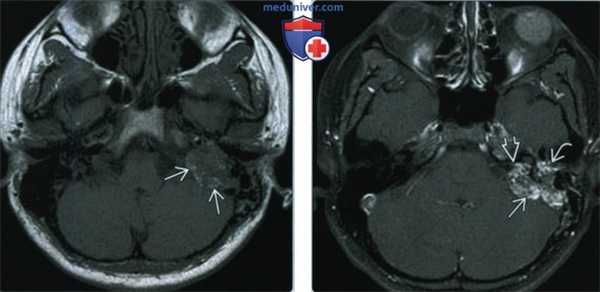

(Слева) При аксиальной МРТ Т1 ВИ визуализируется экспансивное дольчатое объемное образование левой височной кости с участками ↑ Т1 сигнала, которые часто обнаруживаются в ОЭЛМ и обычно расположены на периферии.

(Справа) При аксиальной МРТ Т1 С+ FS у этого же пациента определяется типичное интенсивное неоднородное контрастное усиление, ожидаемое при ОЭЛМ. Эта опухоль также прорастает в левый ВСК, среднее ухо в и сосцевидный отросток. Обратите внимание на диффузный патологический сигнал в левом глазном яблоке, свидетельствующий об ангиоме сетчатки с отслойкой, наблюдающейся при болезни фон Гиппеля-Линдау.